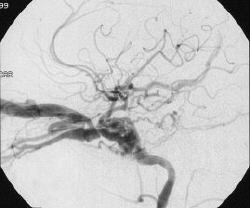

Refer to this picture for question 2

2. Condition that can give rise to this picture include: